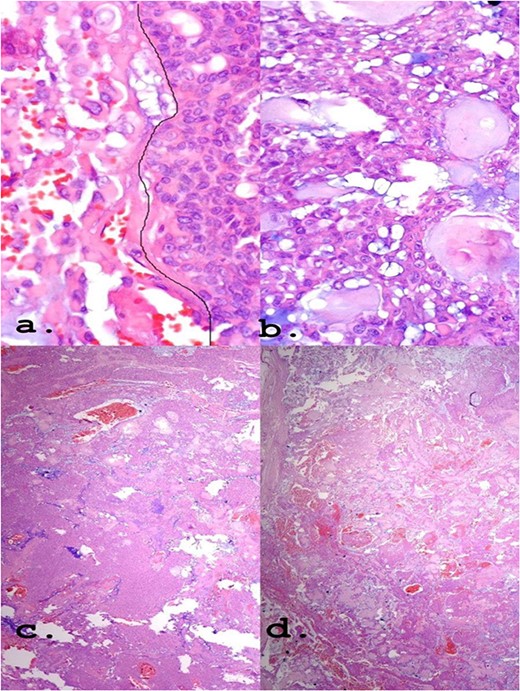

(a) Epithelioid area on the left. (b) Area of triple epithelial cell phenotype (plasmacytoid, myoepithelial and ductal). (c) Highly cellular lesion with a tendency to cellular monomorphism and scarce stromal component. (d) Very limited neoplasm—green India ink—margin surgical HE, ×40.

PA is commonly represented by having wide architectural and cytomorphological diversity. It has cells capable of differentiating into epithelium and myoepithelium, as well as into mesenchymal cells of the chondroid, myxoid and even bone types. The epithelial cells, arranged in an arrangement of cords or leaflets, can be ductal or non-ductal, and the presentation can be predominant with epithelial richness or have only foci of epithelium, thus being variable [7].

Regarding the differentiation between myoepithelioma and PA, the analysis of the presence of ducts is a plausible way of distinguishing since these are rare in myoepitheliomas. Although less frequent, myoepithelioma may present myxoid or chondroid stroma, which bears a resemblance to PA. Some other common findings may make the diagnosis difficult, such as the abundance of myoepithelium and areas with pure myoepithelial cells [5, 8].

The positivity of markers such as p63, myoepithelial cell markers and AE1/AE3, epithelial cells, found in immunohistochemistry (Fig. 4) may also be present in myoepitheliomas but in a lower percentage, ranging from 17 and 44% [8]. However, in this report, a large number of plasmacytoid epithelial cells and mainly ductal formations are superimposable characteristics of the PA, despite the scarce stromal component and foci of myoepithelium.